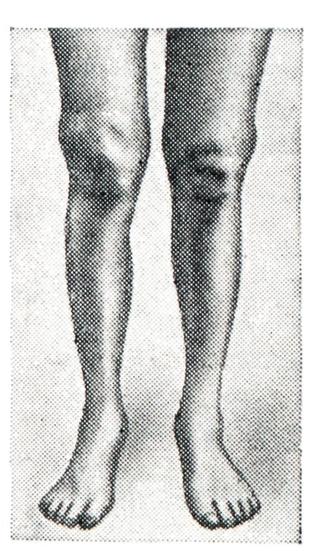

Наиболее характерен метастатический гонит (моноартрит с острым и подострым течением). Морфологически острый гонит может быть серозным или гнойным, подострый — серозно-фибринозным. При всех формах отмечаются мучительные боли, высокая температура, тяжелое общее состояние больного. Развитие патологических изменений в суставе резко выражено: быстро развивается деформация, сгибательные контрактуры (рис. 14), мышечная атрофия. Показатели лабораторных исследований говорят об активности воспалительного процесса. В пунктате можно обнаружить гонококки. При неправильном или запоздалом лечении быстро развивается выраженная деструкция суставных элементов и анкилоз.

Рис. 14. | ||